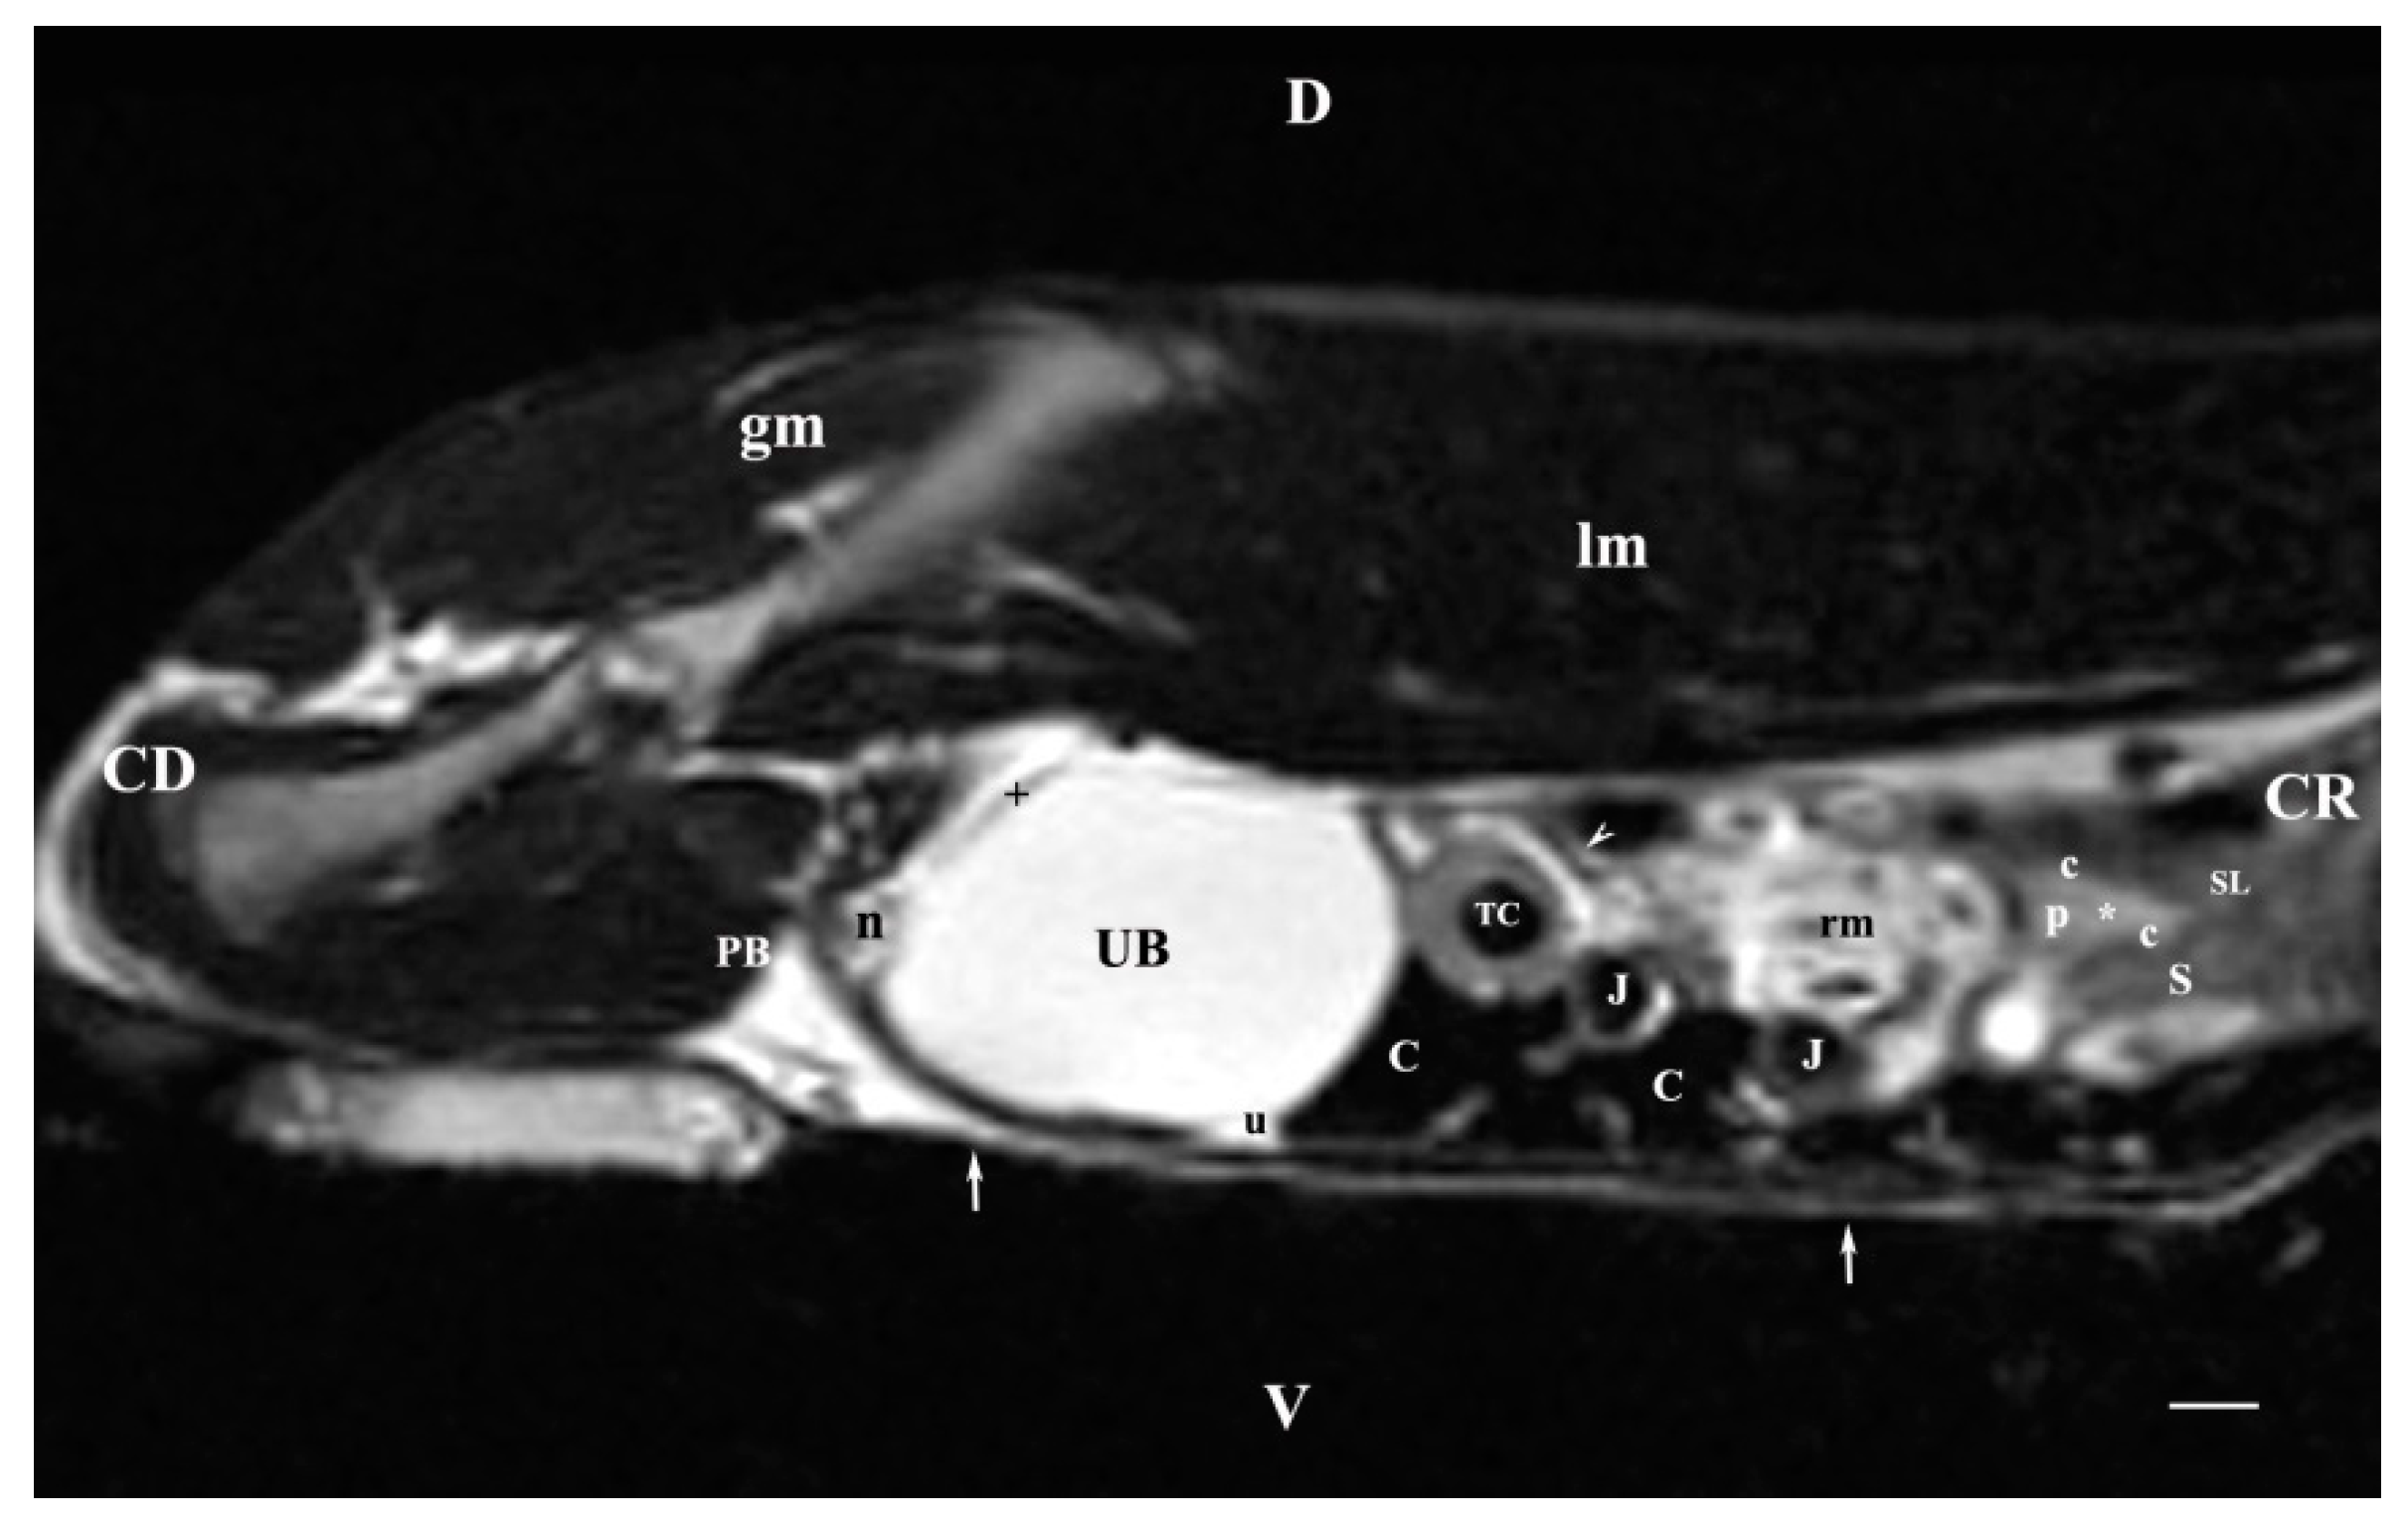

3.2. Sagittal MRI